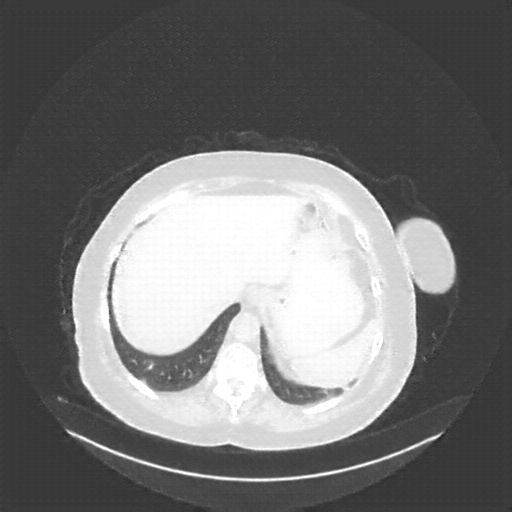

Generated VENOUS CT scan (A→B translation)

No window - Raw intensity values

Lung window (WL -600, WW 1500 β†’ Low βˆ’1350, High +150)

Native→Venous Translation Metrics (Generated Venous vs Real Venous)

Targeted Slice 70 - Network-Normalized Analysis (Generated vs Real Venous)

0.728

SSIM Score

0.241

RMSE

0.105

MAE

Targeted Slice 70 - HU-Space Analysis (Generated vs Real Venous)

HU SSIM

241.4

HU RMSE

104.9

HU MAE